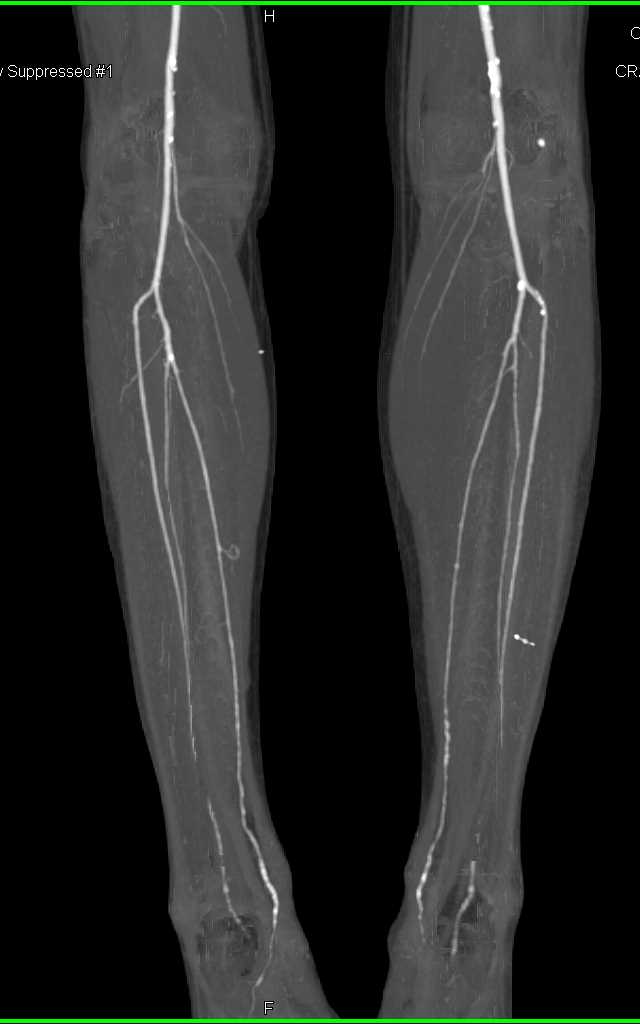

Diagnosis

Aneurysm of the Celiac Artery in 3D